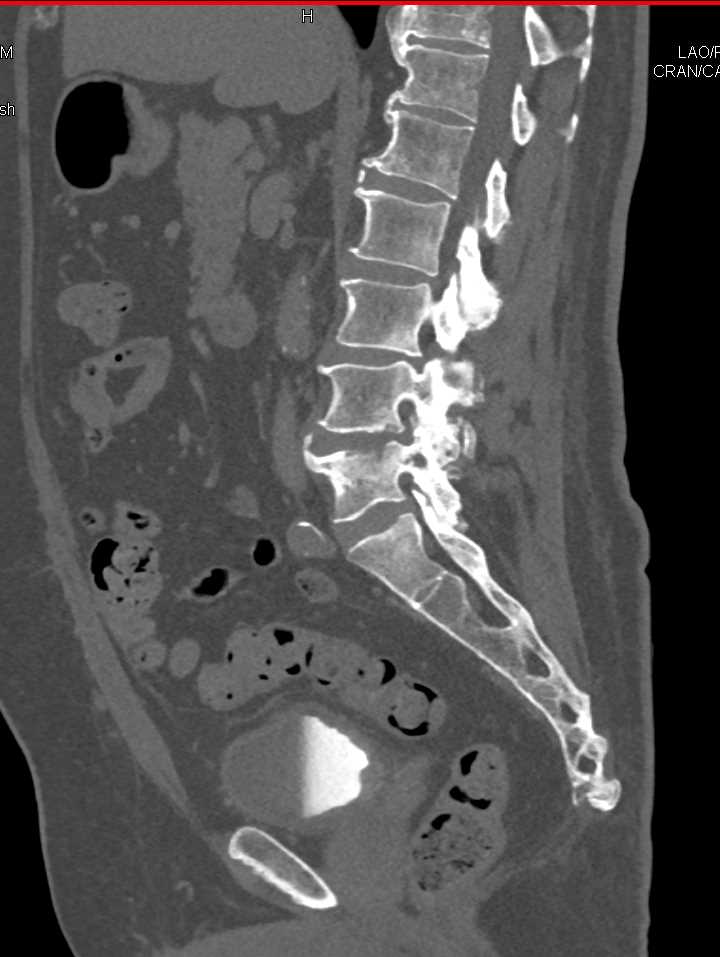

Infection at L4-L5 interspace